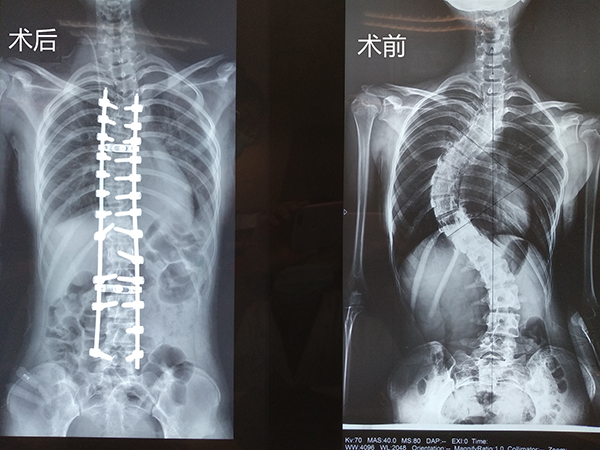

花季少女告別“蝦體型”,重拾自信人生——柳州市人民醫院脊柱骨科團隊成功實施一例脊柱側凸矯形手術

近日,一位14歲的花季少女小孔在父母的陪同下來到了我院脊柱骨科住院治療。小孔的媽媽1年前發現女兒背部畸形,右側背部突出,雙肩不等高。發現之后即到醫院就診,當時的脊柱全長X線片發現:脊柱側凸畸形,衡量側凸的Cobb角約40°。當時小孔因懼怕醫院,未住院系統診治,一直未予重視。今年小孔的背部畸形越發明顯,趁暑假時期,其父母帶著小孔到我院住院治療。

住院查體及檢查發現,小孔脊柱側凸畸形嚴重,雙肩明顯不等高,右側肩胛骨明顯突出,右側胸前凹陷。衡量側凸的Cobb角約75°。且小孔近期輕微活動后即感覺氣喘,體力較前下降。

術前

脊柱骨科主任、主任醫師胡朝暉博士詳細查看病人及檢查結果后認為,小孔脊柱側凸畸形嚴重,進展快,側凸角度較去年明顯增大,影響肺功能,外觀明顯畸形,對小女孩的心理及日常生活已造成嚴重的影響。且畸形很可能進一步加重,壓迫心臟、肺、腹部等臟器,引起呼吸困難等心肺腹問題,還可能會出現頑固性背痛、站立和行走困難、跛行、肢體無力、大小便失禁等癥狀。有強烈的手術指征,需手術對其脊柱側凸畸形進行矯形、固定。

在充分做好術前準備后,由胡朝暉主任主刀順利完成了該手術。術中置入26枚螺釘,術中透視見畸形矯正效果好,歷時近7小時。手術切口長約35公分,為盡可能減少在花季少女身上留下疤痕,均使用美容線一針一線仔細縫合,縫合皮膚時長近2小時。

手術很成功,術后復查脊柱全長X線片可見小孔的脊柱側凸已基本矯正。小孔手術后6天即可下地行走、14天康復出院。小孔手術前與媽媽身高相近,手術后下床發現自己比媽媽高出了“半個頭”,身高從手術前的157cm變為手術后的163cm。小孔背部的畸形也已明顯糾正,雙肩恢復等高,小孔及父母對治療效果都非常滿意。現在的小孔變得自信了很多,她對新學期的到來充滿了期待!

術后